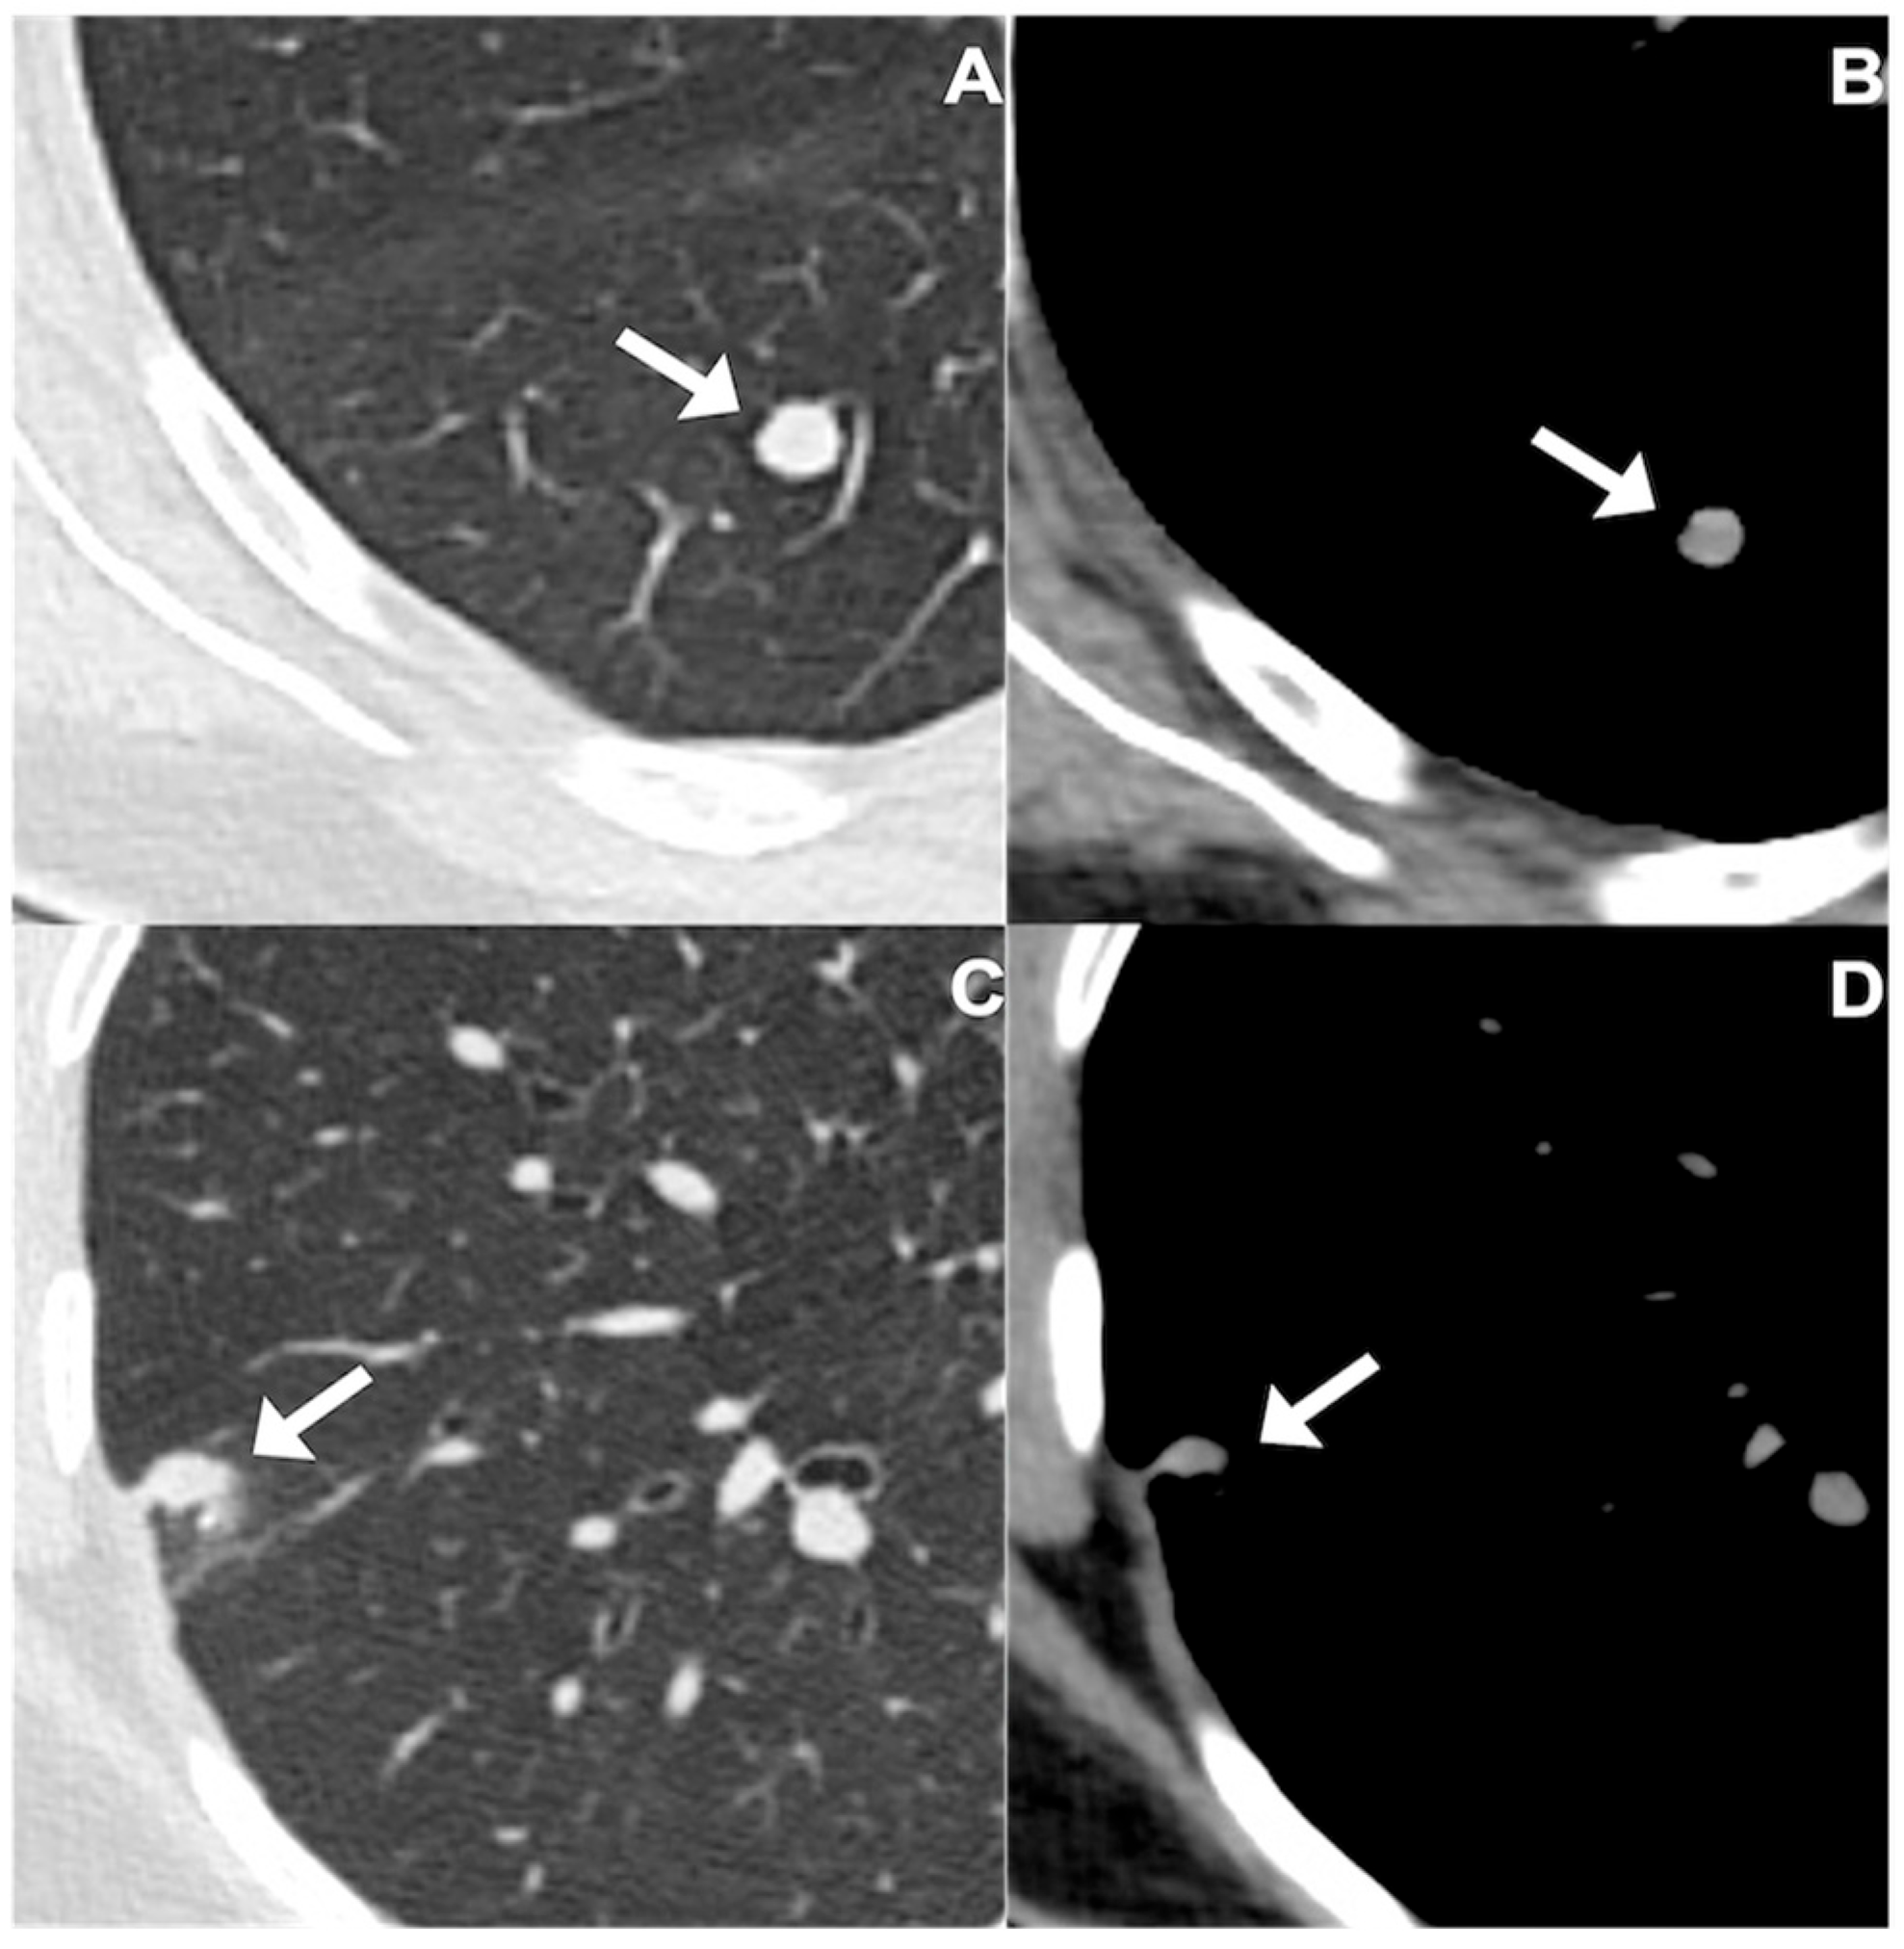

2.3. Evaluation and Segmentation of Chest CT Images